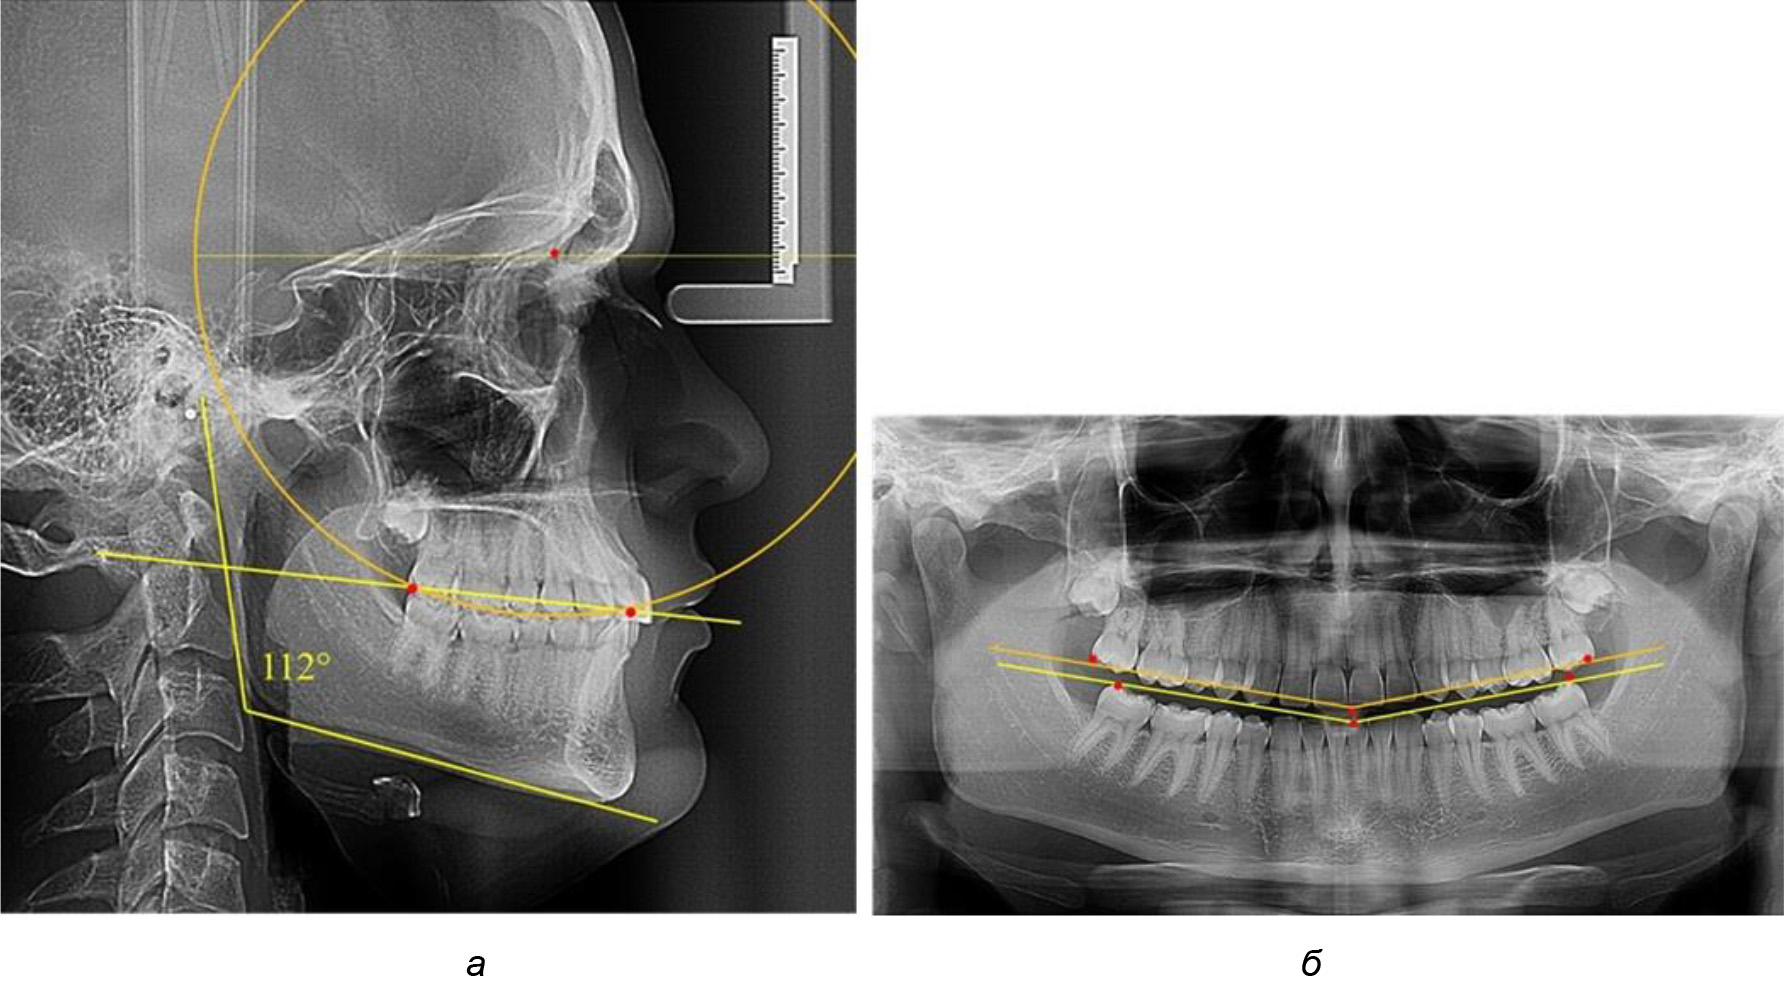

У людей с аномалиями окклюзии по сагиттали в 1-й подгруппе обследовано 9 человек. Обращает на себя внимание увеличение глубины кривой Spee, что нами расценивалось, как патологическая форма кривой линии окклюзии.

Глубина кривой Spee в среднем по 2-й подгруппе составила (5,69 ± 1,57) мм, что было достоверно больше, чем у людей с физиологической окклюзией (р ˂ 0,05). Достоверных различий с показателями, полученными при анализе ТРГ и ОПТГ, нами не отмечено (р ˃ 0,05). Отношение радиуса окружности к сагиттальному размеру окклюзионной линии в среднем по подгруппе составляло 1,372 ± 0,042 и не соответствовало числу Фибоначчи, что может быть использовано в качестве диагностического критерия определения патологической формы кривой Spee. После лечения пациентов техникой «прямой» дуги было отмечено незначительное увеличение сагиттального размера окклюзионной лини в среднем на (2,12 ± 0,77) мм. Однако окклюзионная линия практически касалась окклюзионного контура всех жевательных зубов, и отмечалось практически полное отсутствие кривой Spee.

Таким образом, проведенное лечение техникой «прямой» дуги способствует нормализации окклюзионного равновесия и торку передних зубов, однако не соответствует оптимальному окклюзионному статусу, характеризующему физиологическую окклюзию. При этом величина нижнечелюстного угла оставалась на прежнем уровне (рис. 5).

Рис. 5. Особенности ТРГ при патологической кривой Spee до лечения (а) и после лечения (б) техникой «прямой» дуги

Во 2-й подгруппе 2-й группы было обследовано 7 человек.

Указанная величина не имела достоверного отличия с 1-й подгруппой (р ˃ 0,05), что определяло однородность групп по количественному признаку.

Обращает на себя внимание, что глубина кривой Spee в анализируемой подгруппе практически не отличалась от показателей, полученных у людей с физиологической окклюзией, и составляла (4,23 ± 1,58) мм. Отношение радиуса окружности к сагиттальному размеру окклюзионной линии в среднем по подгруппе составляло 1,623 ± 0,02 и соответствовало числу Фибоначчи.

После лечения пациентов техникой «прямой» дуги, так же как и в 1-й подгруппе, было отмечено увеличение сагиттального размера окклюзионной лини в среднем на (2,38 ± 0,83) мм. Окклюзионная линия практически касалась окклюзионного контура всех жевательных зубов, и отмечалось практически полное отсутствие кривой Spee, так же как и у людей 1-й подгруппы 2-й группы (рис. 6).

Рис. 6. Особенности ТРГ при оптимальной кривой Spee до лечения (а) и после лечения (б) техникой «прямой» дуги

Таким образом, проведенное лечение техникой «прямой» дуги способствует нормализации окклюзионного равновесия и торку передних зубов, однако не соответствует оптимальному окклюзионному статусу, характеризующему физиологическую окклюзию. При этом величина нижнечелюстного угла оставалась на прежнем уровне.